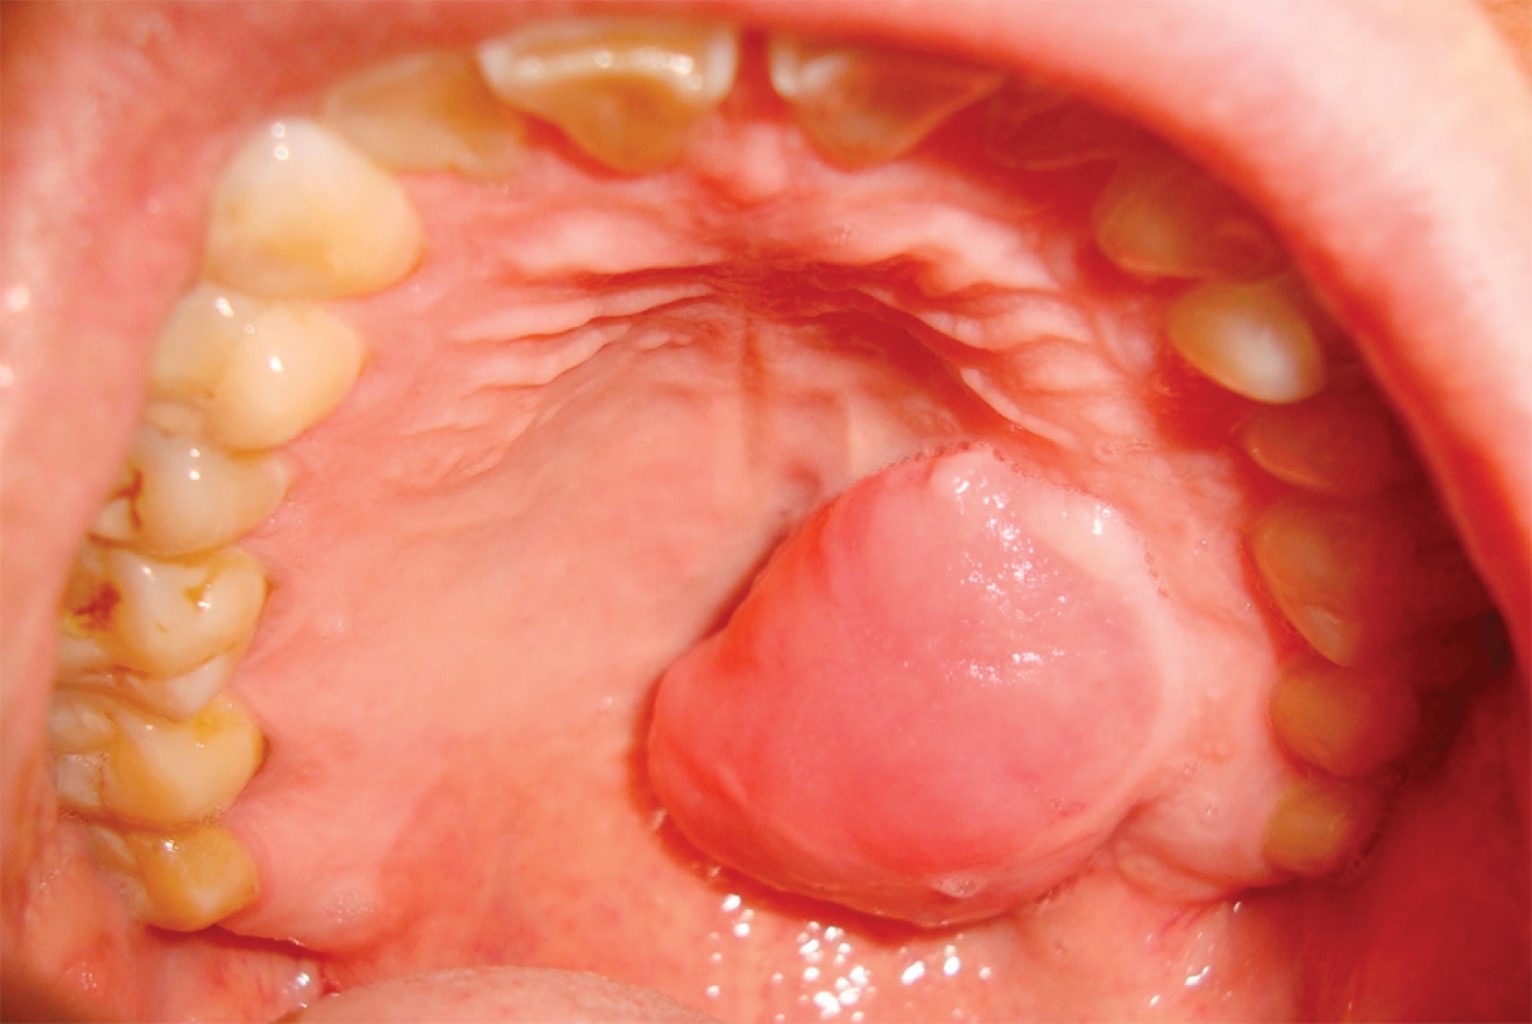

Al examen clínico se observa lesión tumoral en paladar duro, lado izquierdo, de base pediculada que respeta línea media, cuyas dimensiones son 3 cm en sentido latero-lateral por 2.5 cm en sentido anteroposterior (Figura 1). La mucosa que lo recubre no presenta alteraciones de color ni superficie. El paciente no relata cambios significativos de tamaño en los últimos meses. No se evidencia presencia de adenopatías cervicales. Se realiza tomografía de haz cónico donde no se observa compromiso alguno de cortical palatina.

Figura 1